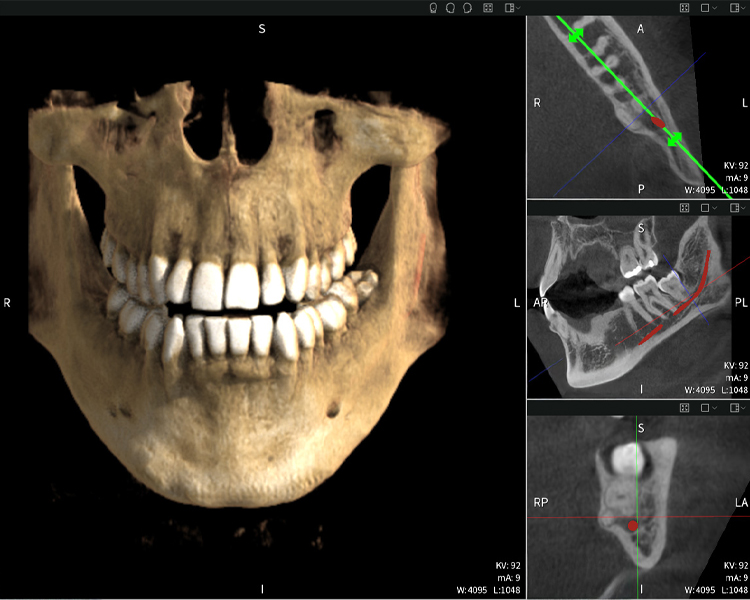

Below you will find a case from Dr. med. dent. Oliver A. Centrella, in which the CBCT images obtained with Seethrough Max provided crucial information on the complex anatomy and the critical relationship between the wisdom teeth and the inferior alveolar nerve. In this case, there is a indication for the surgical removal of the wisdom teeth.

Figure d: Imaging results of Seethrough Max, in front of a black background.

Figure d

Figures b–d show various views of a 3D reconstruction of the mandible, providing a comprehensive overview of the mandibular anatomy, the position of the nerves in relation to the teeth, and allowing assessment of tooth symmetry and alignment.

Figure d shows the previously treated tooth 48, with its crown removed, and its roots left in proximity to the nerve, illustrating the high risk of nerve damage.